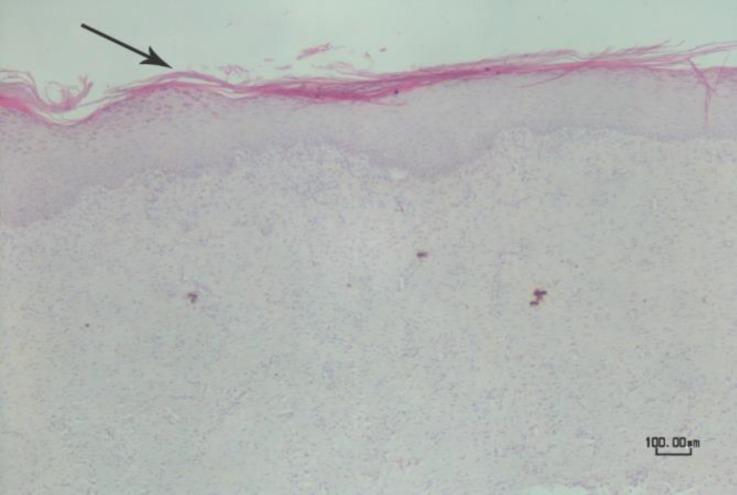

This study was conducted to evaluate the effect of subcutaneous administration of synthetic eugenol (EG) for disbudding of goat kids, as a new chemical method. Thirty apparently healthy Raieni (Cashmere) goat kids (five-day-old) were divided randomly into six groups (n = 5). In the pathology (P) groups (P, P and P according to the sample collection day after injection) an amount of 0.10 mL of EG was subcutaneously administrated in both horn buds. In the disbudding 1 and 2 (DB, DB) groups, 0.10 mL of EG, and in the control (C) group 0.10 mL normal saline was subcutaneously injected in the right horn buds, respectively. Eugenol injection in DB group was done in twelve-day-old goat kids. The left horn buds of DB, DB and C groups were considered as control of horn outgrowing. The horn buds, kidneys, liver, lung, brain and heart, tissue specimens were collected from P and P groups, and bud skin samples were collected from P group. The results showed that the EG was able to stop the horn growth in the first week of goat life. There was no significant difference between left and right horn size in the C group. Histopathological study revealed complete necrosis of bud tissue in dermal and epidermal layers, in P animals. Healing and re-epithelialization were seen in the samples taken from P group. Subcutaneous injection of the synthetic EG can be considered as a new method for goat kids disbudding.

本研究旨在评估皮下注射合成丁香酚(EG)作为一种新的化学方法用于摘除山羊羔角芽的效果。30只外观健康的拉伊尼(开士米)山羊羔(5日龄)被随机分为6组(每组n = 5)。在病理(P)组(根据注射后样本采集日分为P、P和P组),在两个角芽处皮下注射0.10 mL的EG。在去角1组和去角2组(DB1、DB2),分别在右角芽处皮下注射0.10 mL的EG,而在对照组(C组),在右角芽处皮下注射0.10 mL生理盐水。DB组在12日龄的山羊羔中进行丁香酚注射。DB1组、DB2组和C组的左角芽被视为角生长的对照。从P组和P组采集角芽、肾脏、肝脏、肺、脑和心脏的组织标本,从P组采集芽皮肤样本。结果表明,EG能够在山羊生命的第一周阻止角的生长。C组左右角大小之间无显著差异。组织病理学研究显示,P组动物的芽组织在真皮和表皮层出现完全坏死。从P组采集的样本可见愈合和重新上皮化。皮下注射合成EG可被视为一种摘除山羊羔角芽的新方法。